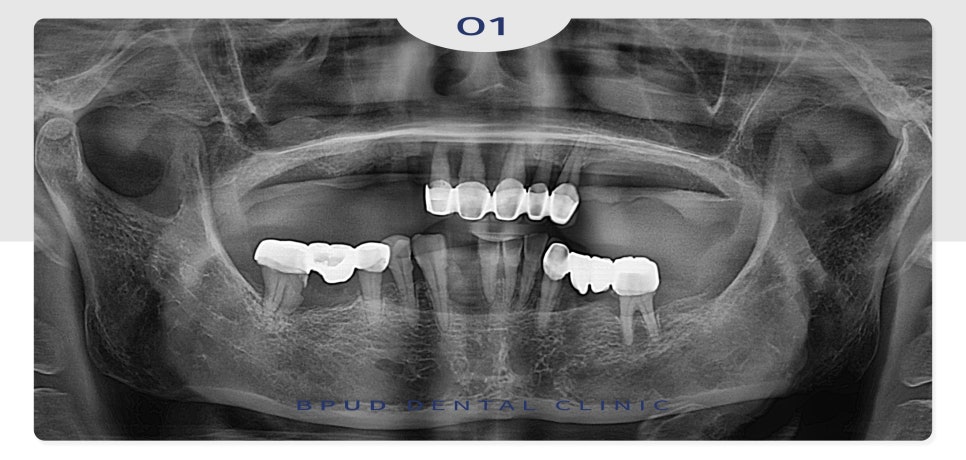

오늘은 부분 틀니를 사용하시다가

전체 임플란트로 교체하신

환자분을 소개해 드리려고 합니다.

위 환자분께서는 오래전부터

위쪽 부분 틀니를 사용 중이셨고

아래 앞니가 자연적으로

발치되신 상태로 틀니를 지지하고

남아 있는 치아들의 동요도도

심하신 상태였는데요.

23.08.31

전체적인 치주염도 심하신 편이라

발치 후 전체 임플란트를 진행하시기로

계획을 수립하였는데요.